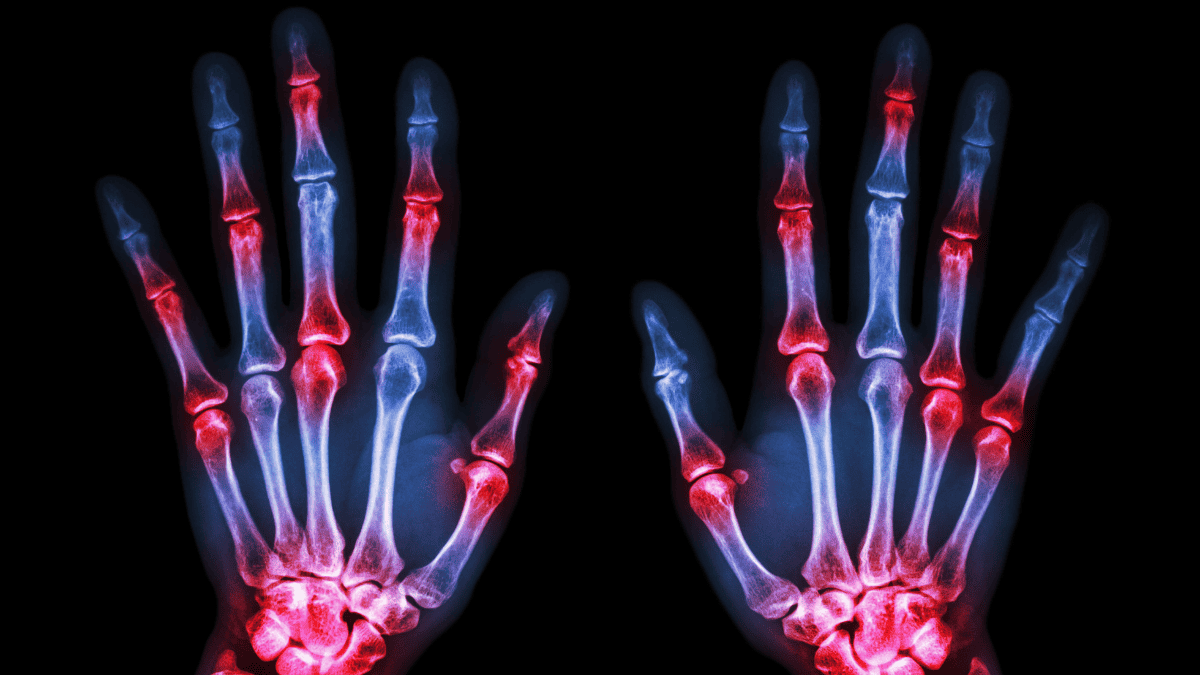

Cientistas desenvolveram uma nova técnica de imagem baseada em emissão de pósitrons (PET) que detecta inflamações pelo corpo antes dos primeiros sintomas surgirem. A tecnologia pode ajudar a tratar doenças, como a artrite reumatoide, previamente.

- Essa técnica produz imagens do corpo que mostram áreas de inflamação, como aquelas causadas pela artrite reumatoide, em todo o corpo.